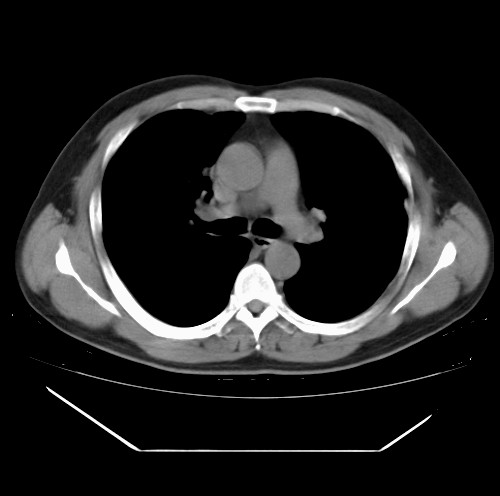

标题: CT22085:双肺多发结节

男,44岁,咳嗽,痰中带血2天。

除肺内及胸膜下可见多发大结节外,在肺小叶中心核、小叶间隔及支气管血管束上亦可见多方小结节,可以认为是随机分布。考虑转移可能性大。

仔细观察病灶形态,病灶边界部分清楚,结合临床症状,首先考虑转移,纵隔内多个肿大淋巴结影。

双肺血管纹理末端多发类圆形结节,边界光滑清晰 气管前腔静脉后淋巴结肿大

考虑转移瘤

沿血管分布,位于血管末端。转移瘤多见,血行性菌栓也可见到。

本例双肺多发类圆形高密度灶,边清,结合病史多考虑双肺多发转移改变,可以结合实验室检查。